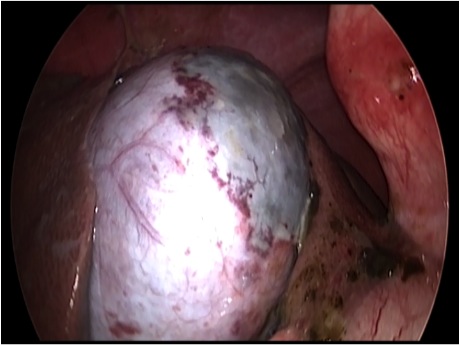

胆嚢が破裂した様子を腹腔内にカメラを入れて観察した像です。

胆嚢から漏れ出た胆汁が腹腔内に確認できます

体の外に出すためお腹の中で袋に入れていきます。

このときに胆嚢と一緒にクリップやガーゼも回収します。

回収袋にいれて体外に摘出していきます。

回収袋にいれて終わりになります。